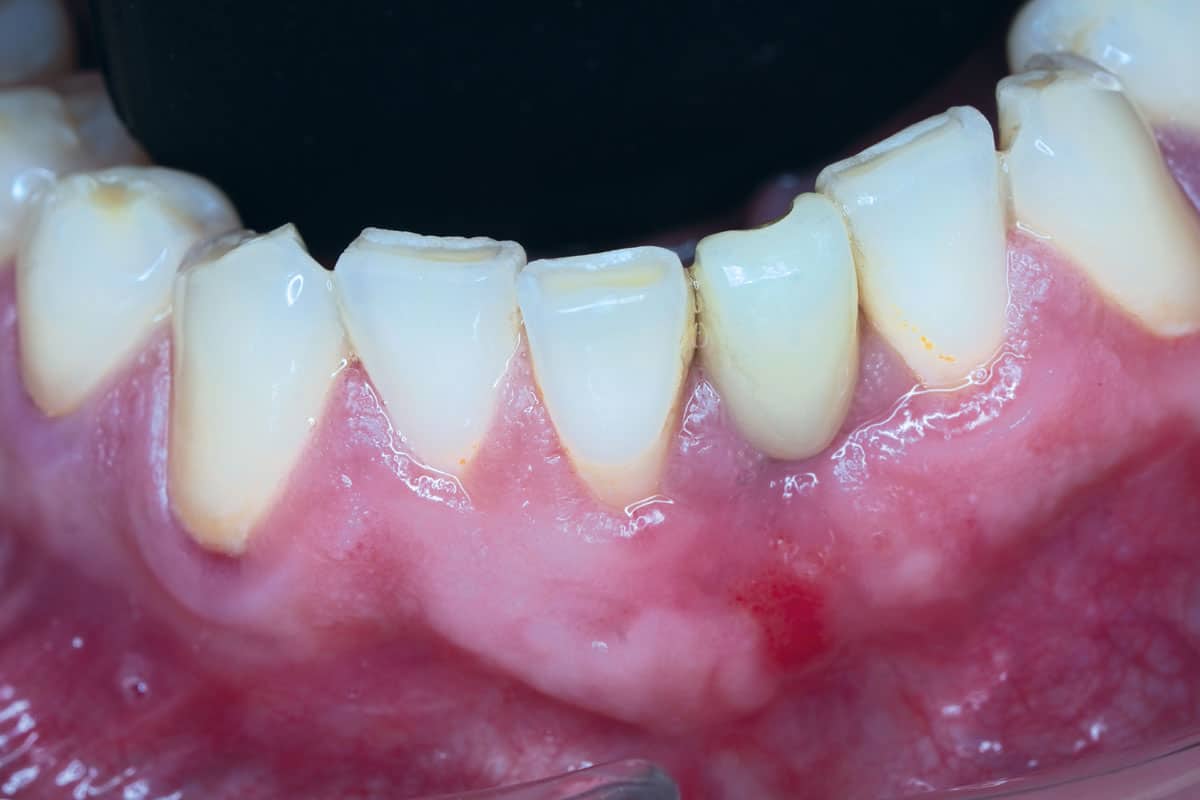

A patient presented with severe gingival recession and pronounced inflammation affecting tooth #24. Following extraction of the tooth and thorough debridement of the infected site, a complete loss of the vestibular wall and a slight resorption of the lingual wall were identified. In this situation, NOVAMag® membrane was cut to shape and given a suitable convexity and used as a rigid plate and fixated with two resorbable NOVAMag® fixation screws. The membrane was fixated of the lingual side only in this case. A narrow ⌀ 3.2 × 13 mm implant was placed. The remaining peri-implant gaps were filled with maxgraft® granules, and the augmentation site was finally covered with a collprotect® membrane.

Follow-up CBCT scans taken at 4 and 9 months demonstrated stable bone regeneration and preservation of the ridge contour in its natural form on the buccal side where the membrane was placed. Deeper placement of the implant initially would have been better. Satisfactory closure of the initial gingival recession was achieved despite minimal mucogingival intervention.